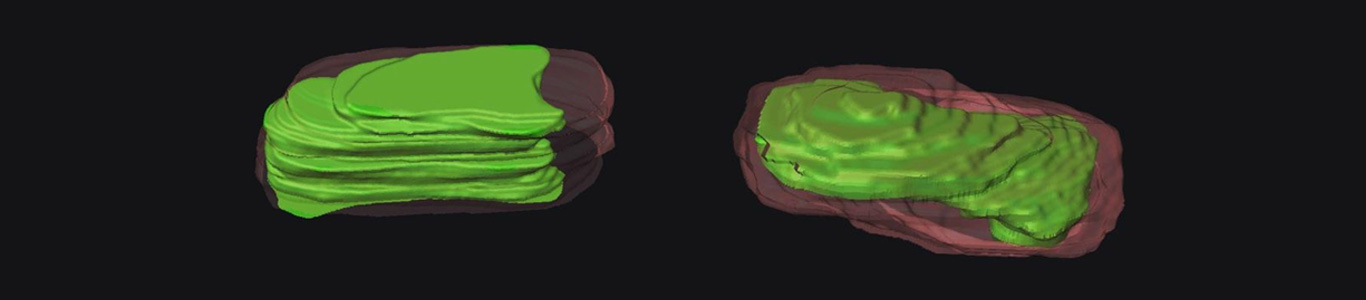

Predicting artery plaque rupture

Due to lipid build up in artery walls, plaques form that can rupture and cause significant health problems for patients. Researchers at the Baker institute have worked together with MCN to study and predict the likelihood of plaque rupture in an attempt to prevent it.